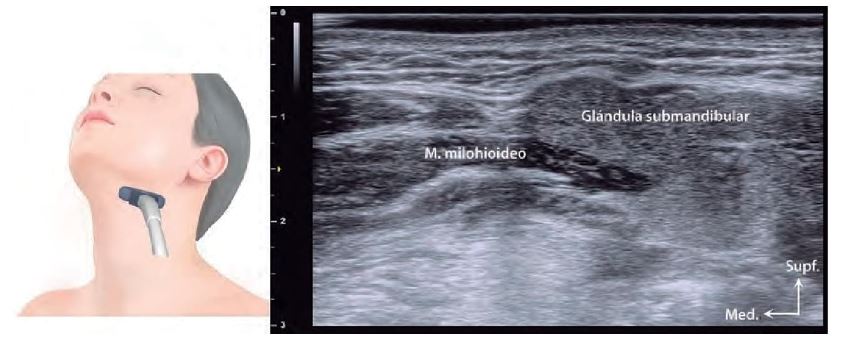

El conocimiento del grosor de la piel, que varía entre regiones como el párpado superior (0,38–0,80 mm) y la punta nasal (1,22–2,01 mm), es fundamental para ajustar técnicas de inyección y procedimientos quirúrgicos. Además, la localización precisa de glándulas salivales (parótida, submandibular y sublingual) mediante ecografía evita complicaciones durante intervenciones en la región mandibular y cervical.